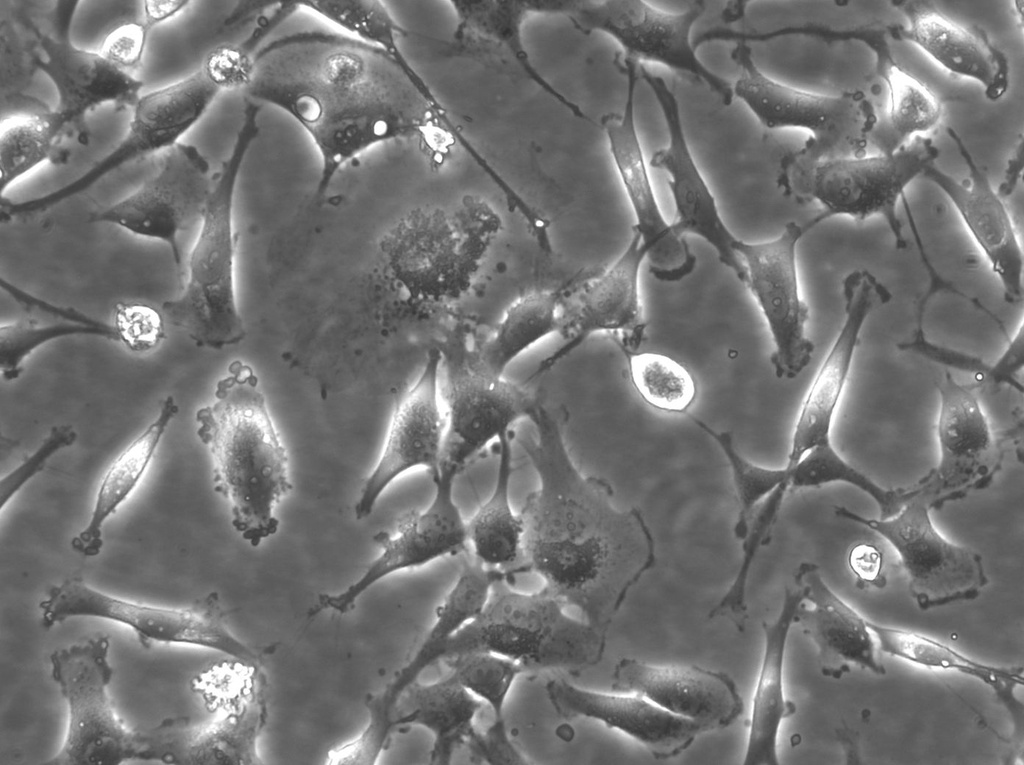

BT-549 Cells

Internal Reference: MA-GEN-BT-549